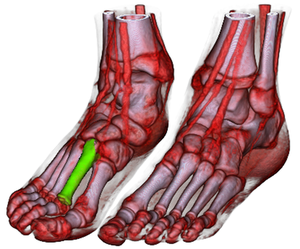

The LiveSync interaction metaphor synchronizes the 2D slice view with the volumetric view to improve the efficiency of diagnosis in the clinical routine. The generation of a meaningful 3D visualization is desirable because often there is not enough contextual information provided by the slice views only. While it is easy to navigate through the slices, the interaction effort to adjust the parameters for the volumetric view is rather high. Some of the major time-consuming tasks are the localization of the feature of interest, the setup of a good viewpoint, the removal of occluding structures via clipping geometries and the adjustment of the zoom factor. LiveSync extracts the needed information to set up all these parameters by a simple picking on a structure of interest in the slice view. In this paper we present substantial enhancements of the existing concept. First, an efficient parametrization for the derived parameters is presented which allows hierarchical refinement of the search space for good views. Second, the extraction of the feature of interest is performed in a way which is adapting to the volumetric extent of the feature. The properties of the extracted features are utilized to adjust a pre-defined transfer function in a feature-enhancing manner. Third, new interaction modes are presented which allow the integration of more knowledge about the user-intended visualization without increasing the interaction effort. Finally, a new clipping technique is integrated which guarantees an unoccluded view on the structure of interest while keeping important contextual information.Additional Files and Images